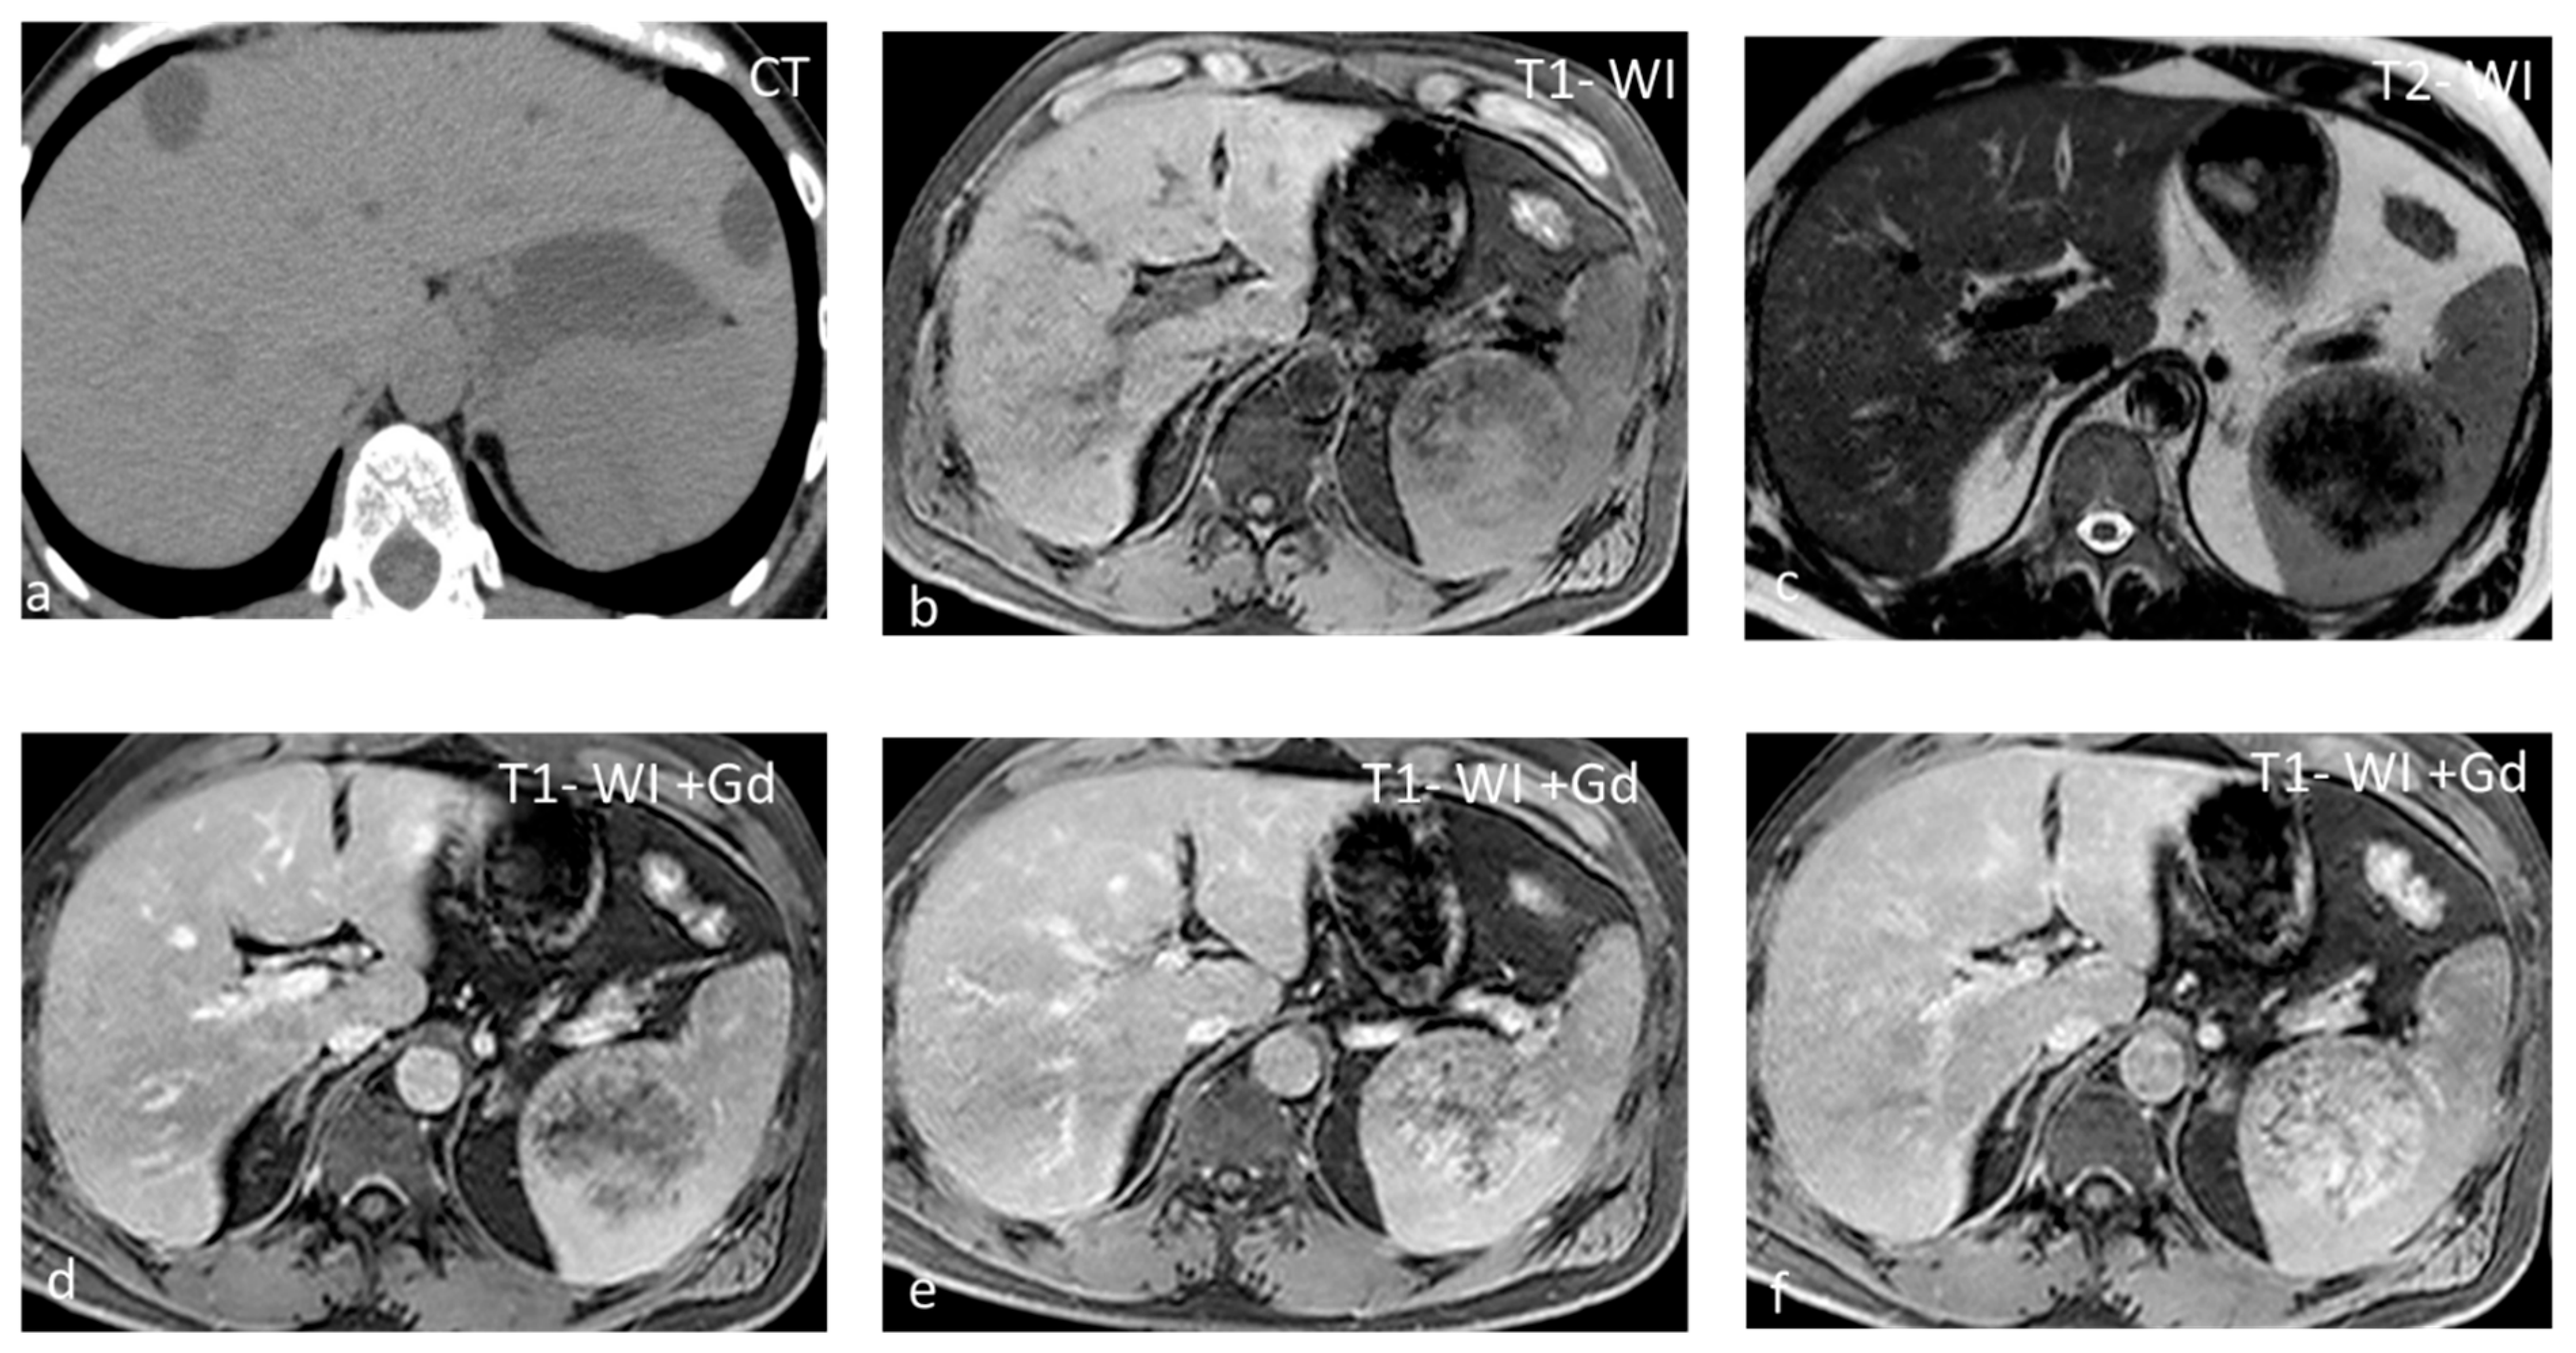

Cysts, most often solitary, are usually incidental findings, being asymptomatic [25]. Two categories exist: primary (true) and secondary (false). Primary cysts, also called epidermoid cysts, are congenital lesions with an epithelial lining, with a 20% prevalence in females. Possible explanations for the pathogenesis of true cyst include (1) infolding of peritoneal mesothelium after rupture of the splenic capsule, (2) collections of peritoneal mesothelial cells trapped in splenic sulci, or (3) origin from normal lymph spaces [27]. Primary splenic cysts constitute 10% of all nonparasitic cysts of the spleen. It is a rare condition with an incidence rate of 0.07%, as reported in a review of 42,327 autopsies [28]. Secondary cysts are lined by a fibrous wall and most often are post-traumatic. Rarely they may occur in splenic abscess or splenic infarction [29]. At ultrasound (US), cysts appear as well-defined rounded lesions with a thin wall and anechoic fluid content. They appear homogeneously hypoattenuating on CT and lack enhancement. Calcifications may be seen in the wall in post-traumatic cysts. Unless hemorrhage or debris is present, at MRI, splenic cysts appear hypointense on T1-WI and homogeneously hyperintense on T2-WI (Figure 4). Simple cysts, either primary or secondary, do not warrant further follow-up with imaging. However, due to the increased risk of complications (rupture, infection, hemorrhage), splenic cysts larger than 5 cm or symptomatic ones should be treated surgically, trying to preserve as much of the splenic parenchyma as possible [30].

Figure 4.

Large splenic cyst appearing homogeneously hypodense on non-contrast CT (a). The cyst content is homogeneously hyperintense on T2-WI (b) and hypointense on T1-WI (c). The cyst wall does not show significant enhancement (d).